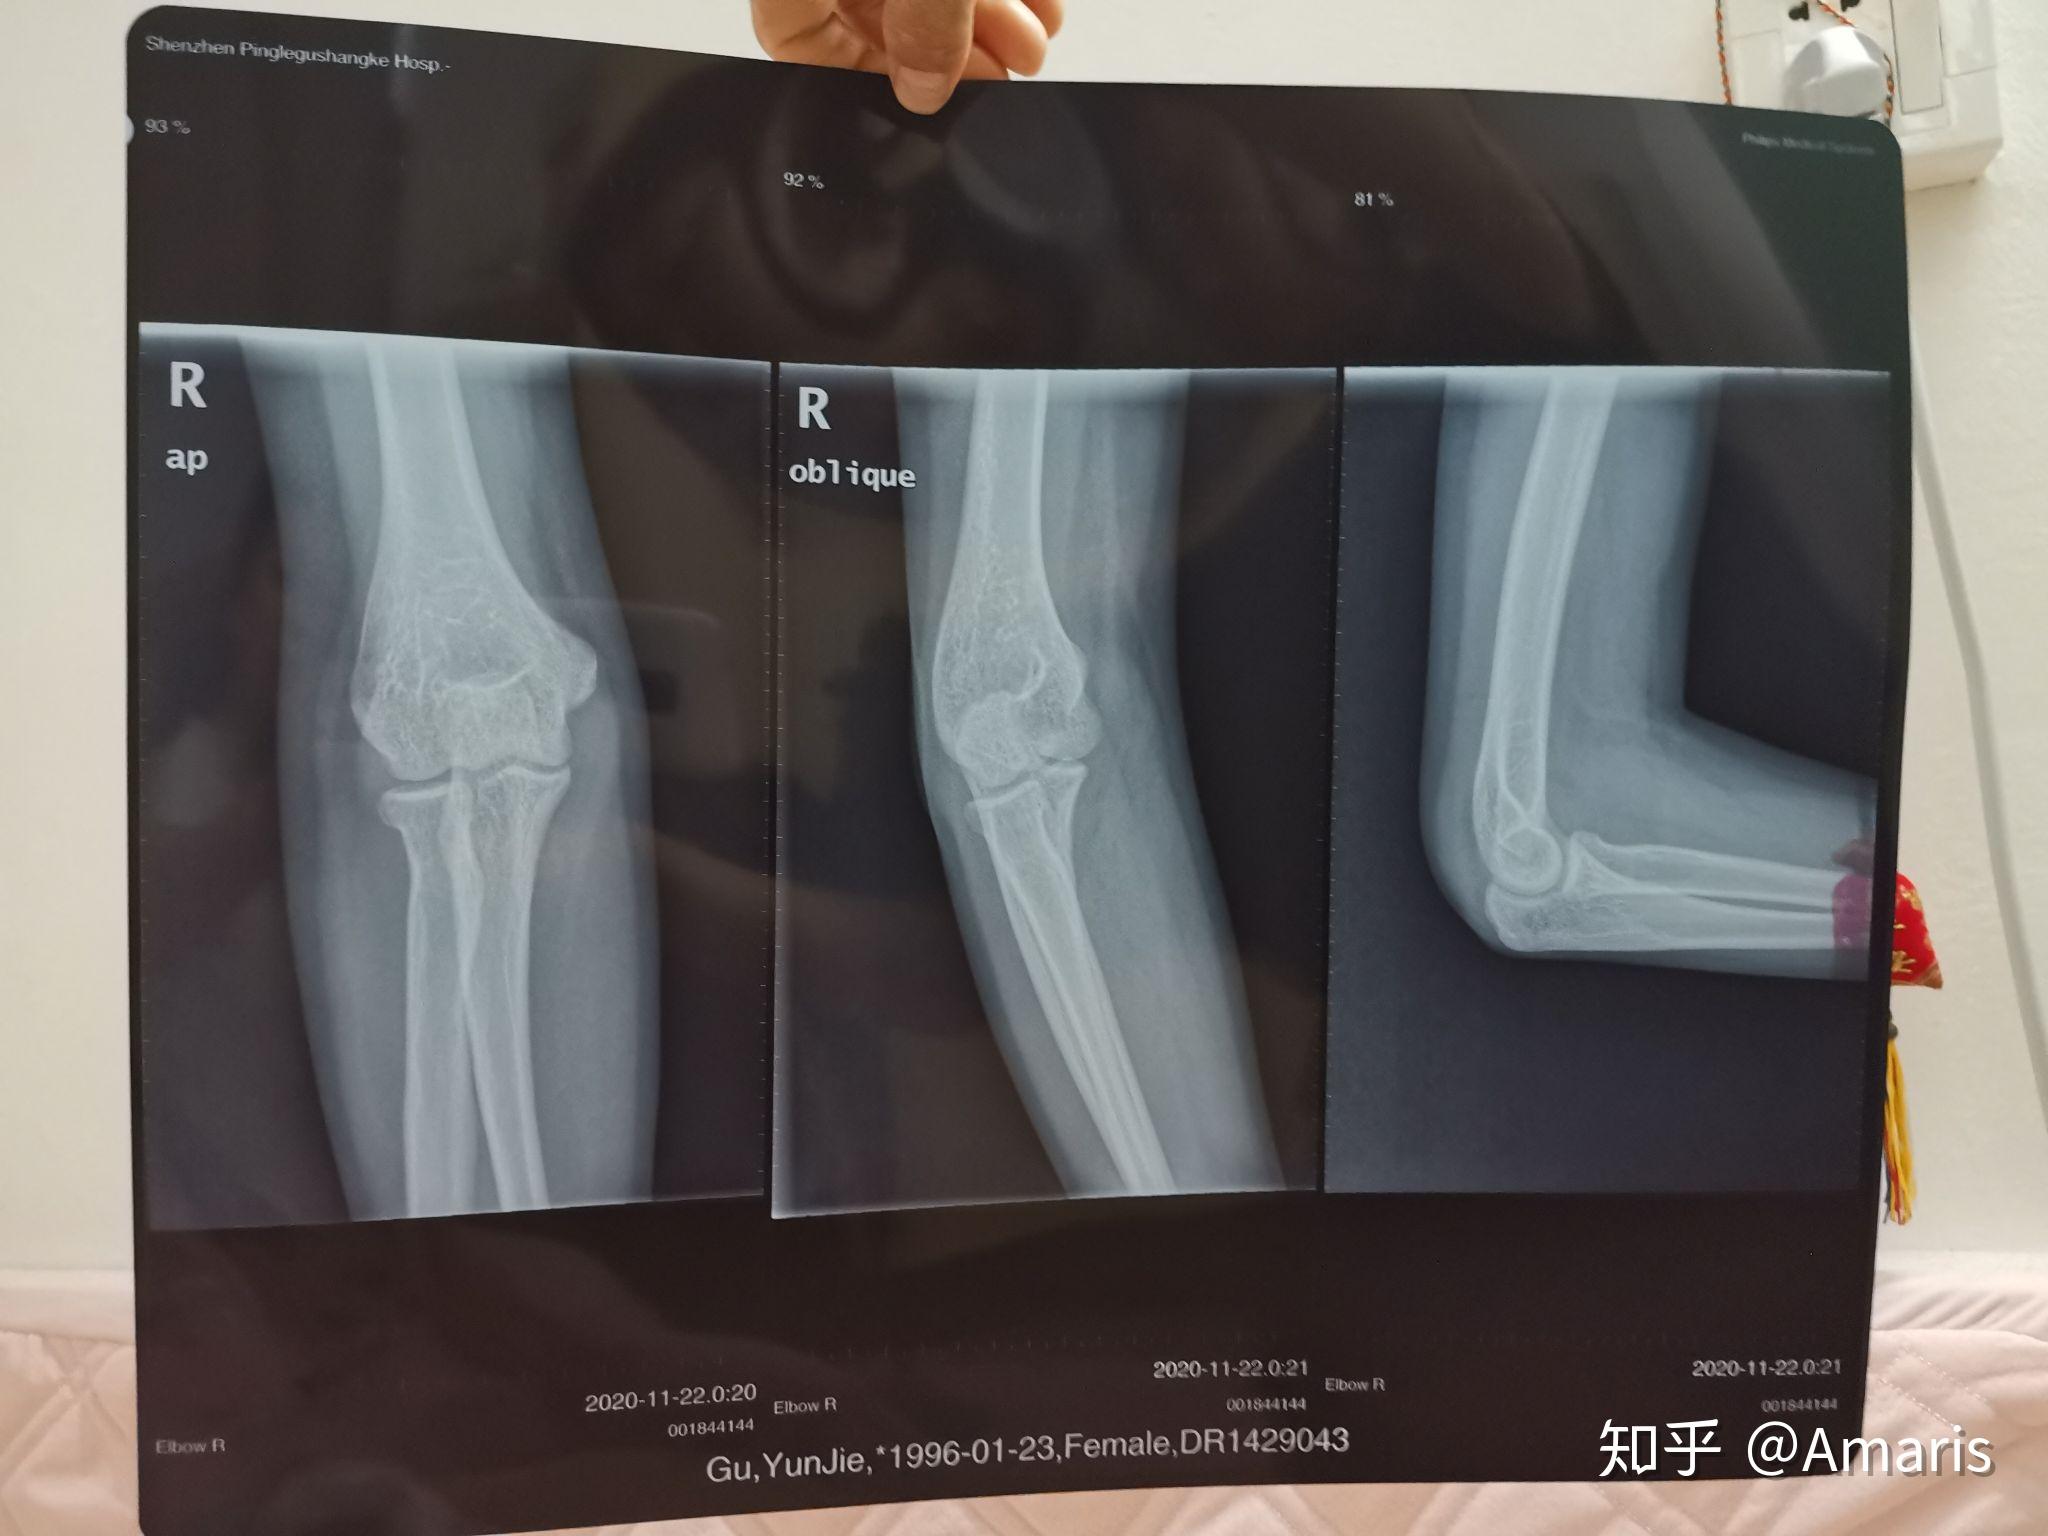

胳膊拍的片子照片,右胳膊拍片子图片

胳膊肘饶骨小头骨折,疑似鹰嘴也骨折,这是带支具一个月拍的片子,请问